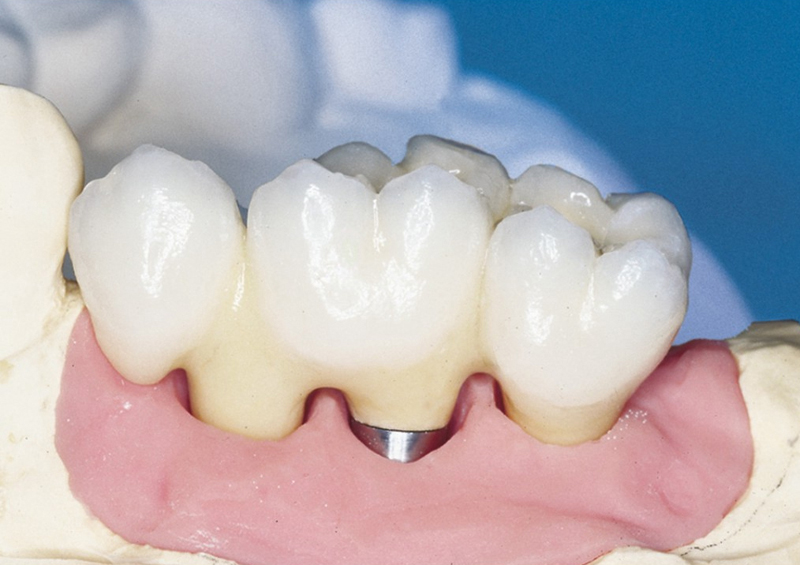

Protetické řešení může být pomocí můstku, který je kotvený na implantátech nebo pomocí jednotlivých korunek na implantátech.

V zásadě je možné do těchto můstků zařadit i přirozené zuby, zejména pokud je potřeba tyto zuby ošetřit proteticky

- korunkami. Korunky nebo můstky mohou být na implantáty nacementovány nebo přišroubovány.

Zdravé zuby zůstanou zachovány a přitom náhrady jsou pevné, jako na vlastních zubech